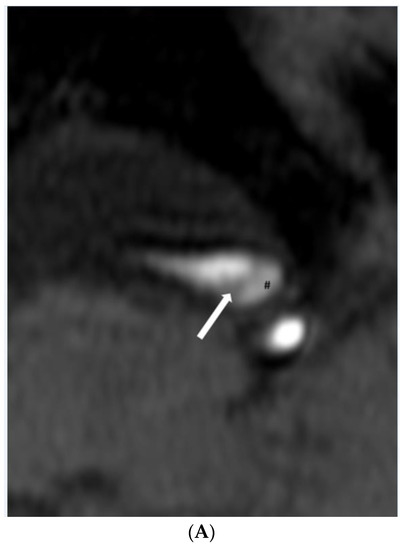

Illustration of HR-VWI between intraplaque hemorrhage and dissection. Dissection shows a similar signal intensity between the true lumen and false lumen on time of flight and black blood T2-weighted imaging. Note: black arrow, fibrous cap; white arrow, intimal flap; *, lumen, $, intraplaque hemorrhage; #, false lumen.

(A,B). Dissection. (A) Time-of-flight imaging shows a similar high signal intensity between the true lumen and false lumen (#). Note the intimal flap with low signal intensity (white arrow). (B) Black blood T2-weighted imaging shows a similar low signal intensity of true and false lumen (#) between the intimal flap (white arrow). (C,D). Intraplaque hemorrhage. (C) Intraplaque hemorrhage ($) on time-of-flight imaging shows a relatively subtle high signal intensity compared to the high signal intensity of the lumen. Note the fibrous cap with low signal intensity (white arrow). (D) Plaque of basilar artery on black blood T2-weighted imaging shows the iso signal intensity compared to the low signal intensity of the lumen.